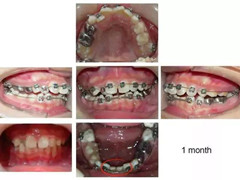

下颌的前牙部分四颗门牙大小不一,乳牙的形态、宽度跟恒牙都不一样,如果不考虑生长发育直接排齐牙齿会增加将来的种植难度,现有的宽度来说,种一颗间隙太大,种两颗太拥挤。操作中,把下颌牙齿用弹簧箍推开,有一定缝隙产生后用填补蛀牙的树脂材料将牙齿堆叠成与左右牙齿一样的宽度。乳牙部分并没有加箍,后面磨牙部分如果咬合关系正常无需移动。

经过一段时间,缺恒牙的乳牙还是会掉。到4-5年后,先天缺失的乳牙开始脱落。此时修改维持器一方面作为空间维持器,一方面用做假牙的材料堆叠做成类似活动假牙。